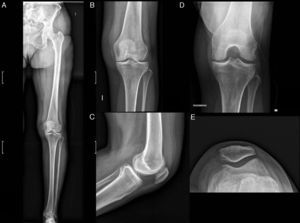

El diagnóstico se realiza mediante la evaluación clínica por un especialista, complementada con estudios de imagen como radiografías o ecografías para valorar el grado de desgaste articular.